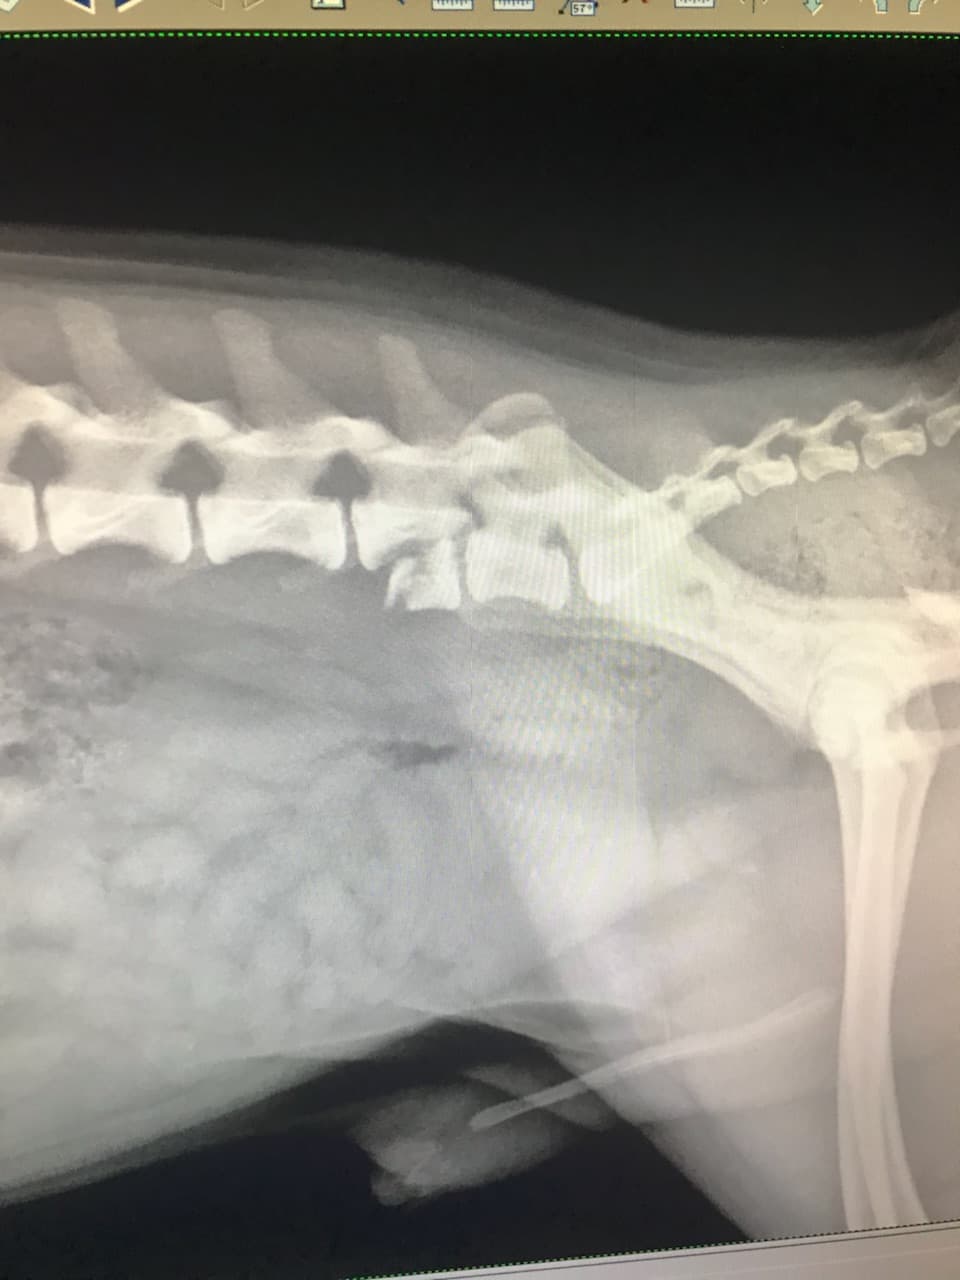

05/03/18- When I was at work, Maple got out of the house and ran out into the street (Bolsa and Bushard) and was hit by an oncoming vehicle. Fortunately Maple survived but was left with a broken leg and damaged spine. The vet said that it would cost 3k for the leg surgery and 7k for the spine surgery and I don't have the money to pay for his medical expenses. I know that people are always fundraising for other causes but if you can even spare a dollar, I would really appreciate it. He's the reason I wake up everyday with a smile. He's the happiest dog in the world and seeing him so sad breaks my heart =((